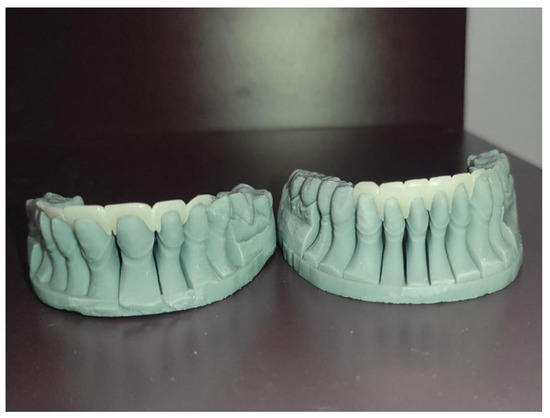

Objectives: The aim of this study was to present and describe a digital workflow integrating Digital Smile Design (DSD) with computer-aided design/computer-aided manufacturing (CAD/CAM) and additive manufacturing technologies for the fabrication of dental preparation guides, focusing on workflow feasibility, design reproducibility, and [...] Read more.

Objectives: The aim of this study was to present and describe a digital workflow integrating Digital Smile Design (DSD) with computer-aided design/computer-aided manufacturing (CAD/CAM) and additive manufacturing technologies for the fabrication of dental preparation guides, focusing on workflow feasibility, design reproducibility, and clinical handling. Materials and Methods: A digital workflow was implemented using intraoral scanning and Exocad DentalCAD 3.1 Elefsina software to design dental preparation guides based on digitally planned restorations. Preparation margins, insertion paths, and minimal material thickness were defined virtually. The guides were fabricated using both subtractive (PMMA milling) and additive (stereolithographic-based 3D printing) manufacturing techniques. Post-processing included chemical cleaning, support removal, additional light curing, and manual finishing. The evaluation was qualitative and descriptive, based on visual inspection, workflow performance, and guide adaptation to printed models. Results: The proposed digital workflow was associated with consistent fabrication of preparation guides and predictable transfer of the virtual design to the manufactured guides. Digital planning facilitated clear visualization of preparation margins and insertion axes, supporting controlled and minimally invasive tooth preparation. The workflow demonstrated good reproducibility and efficient communication between clinician and dental technician. No quantitative measurements or statistical analyses were performed. Conclusions: Within the limitations of this qualitative feasibility study, the integration of DSD with CAD/CAM and 3D printing technologies represents a viable digital approach for designing and fabricating dental preparation guides. The workflow shows potential for improving predictability and communication in restorative dentistry. Full article